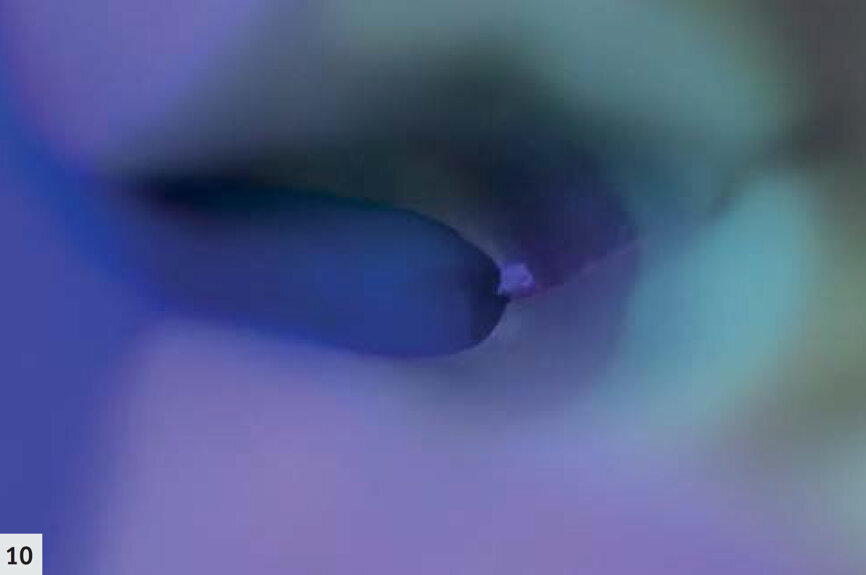

Fig. 10 : D-Light Pro en mode détection permet de confirmer que les limites marginales de la préparation sont toutes positionnées dans l’émail sain. Il ne reste qu’une fissure extrêmement fine, limitée à l’émail.

Une autre dent présentait une profonde fissure au niveau de la limite proximale (Fig. 6). Après le nettoyage (Fig. 7), la structure était mieux visible grâce à la lampe D-Light Pro en mode détection. La structure des tissus dentaires est devenue plus apparente, la dentine émettant davantage de fluorescence dans une couleur verte bien distincte. À ce moment, on pouvait clairement observer la propagation de la fissure dans les couches plus profondes de l’émail, ainsi que dans la dentine (Fig. 8). La fissure a été mieux nettoyée puis préparée à l’aide du dispositif AquaCare Twin (Velopex) chargé avec une fine poudre de coupe d’oxyde d’aluminium, sous pression d’air et refroidissement par eau (Fig. 9). En mode détection, il est possible de confirmer en un coup d’oeil que les limites marginales de la préparation sont toutes positionnées dans l’émail sain (Fig. 10). La fissure extrêmement fine que l’on peut observer est superficielle et limitée à l’émail.